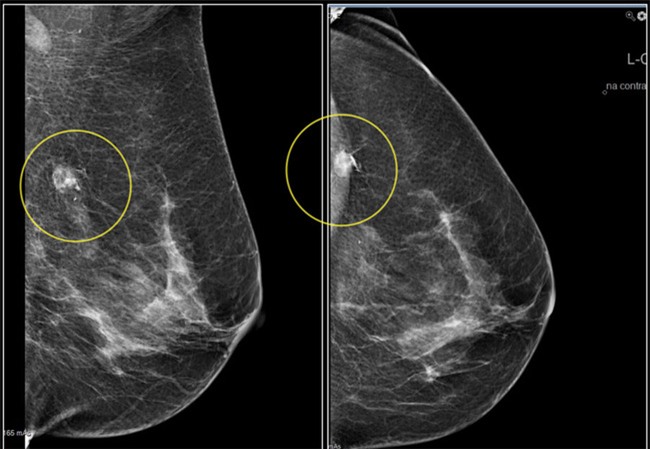

Khi bắt đầu bước sang tuổi 30, phụ nữ nhất định phải tập thói quen tự kiểm tra ngực hàng tháng. Cách đơn giản để phát hiện những bất thường là đứng trước gương tự sờ ngực và nằm ngửa sờ nắn ngực xem có những u cục lạ không. Nếu xuất hiện những cơn đau ngực bất thường, cần phải đi khám sớm để bác sĩ chẩn đoán kịp thời.

Ảnh: Internet

Nếu trong gia đình có chị em từng bị ung thư vú thì bạn nên cẩn thận đi xét nghiệm sớm. Phụ nữ sinh con muộn sau tuổi 30, người nghiện thuốc lá, uống rượu và bia cũng sẽ có nguy cơ mắc ung thư vú cao hơn.

Phụ nữ từ 40 tuổi trở lên là đối tượng dễ bị mắc bệnh ung thư vú cao gấp 3 lần so với những độ tuổi khác. Vì thế, phụ nữ cần chọn cho mình chế độ ăn uống, ngủ nghỉ, tập thể dục hợp lý và và nhất là phải thường xuyên khám ngực định kì.